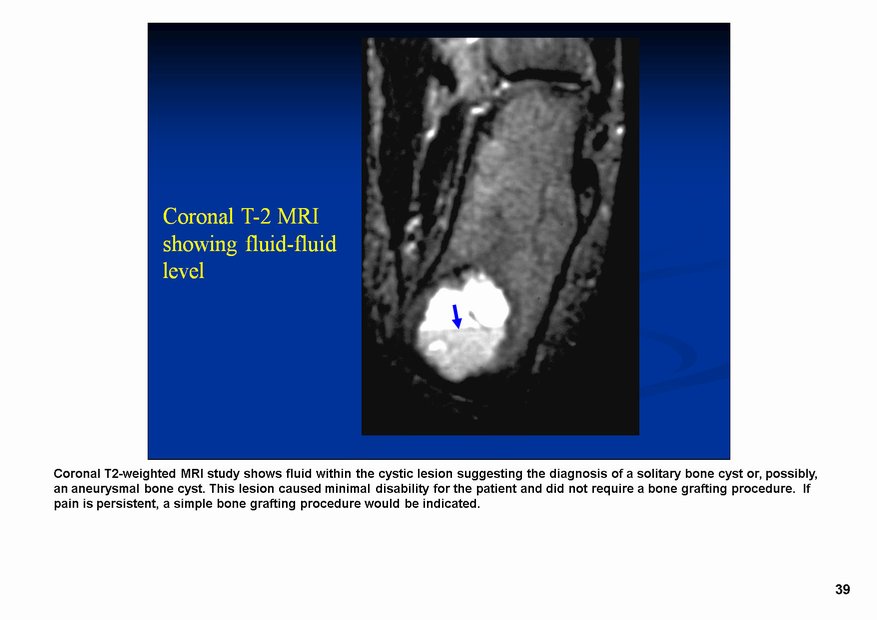

По поводу кисты пяточной кости -

Липома пяточной кости

Из архива AFIP

Липома внутрикостная.

Продолжение.

fibroma.jpg

fibroma.jpg166.11 кб

kostnaya_kista.jpg

kostnaya_kista.jpg86.5 кб